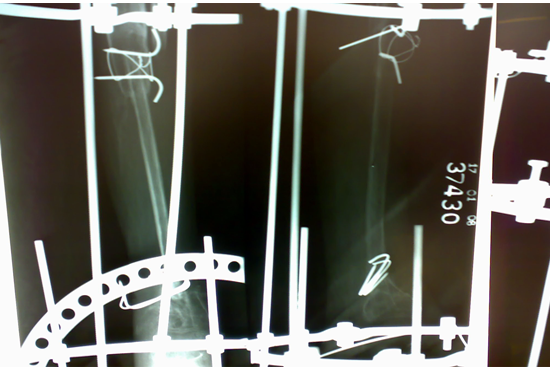

Tibialisation Of Fibula

Shankar Giri

Sudama

Wagh